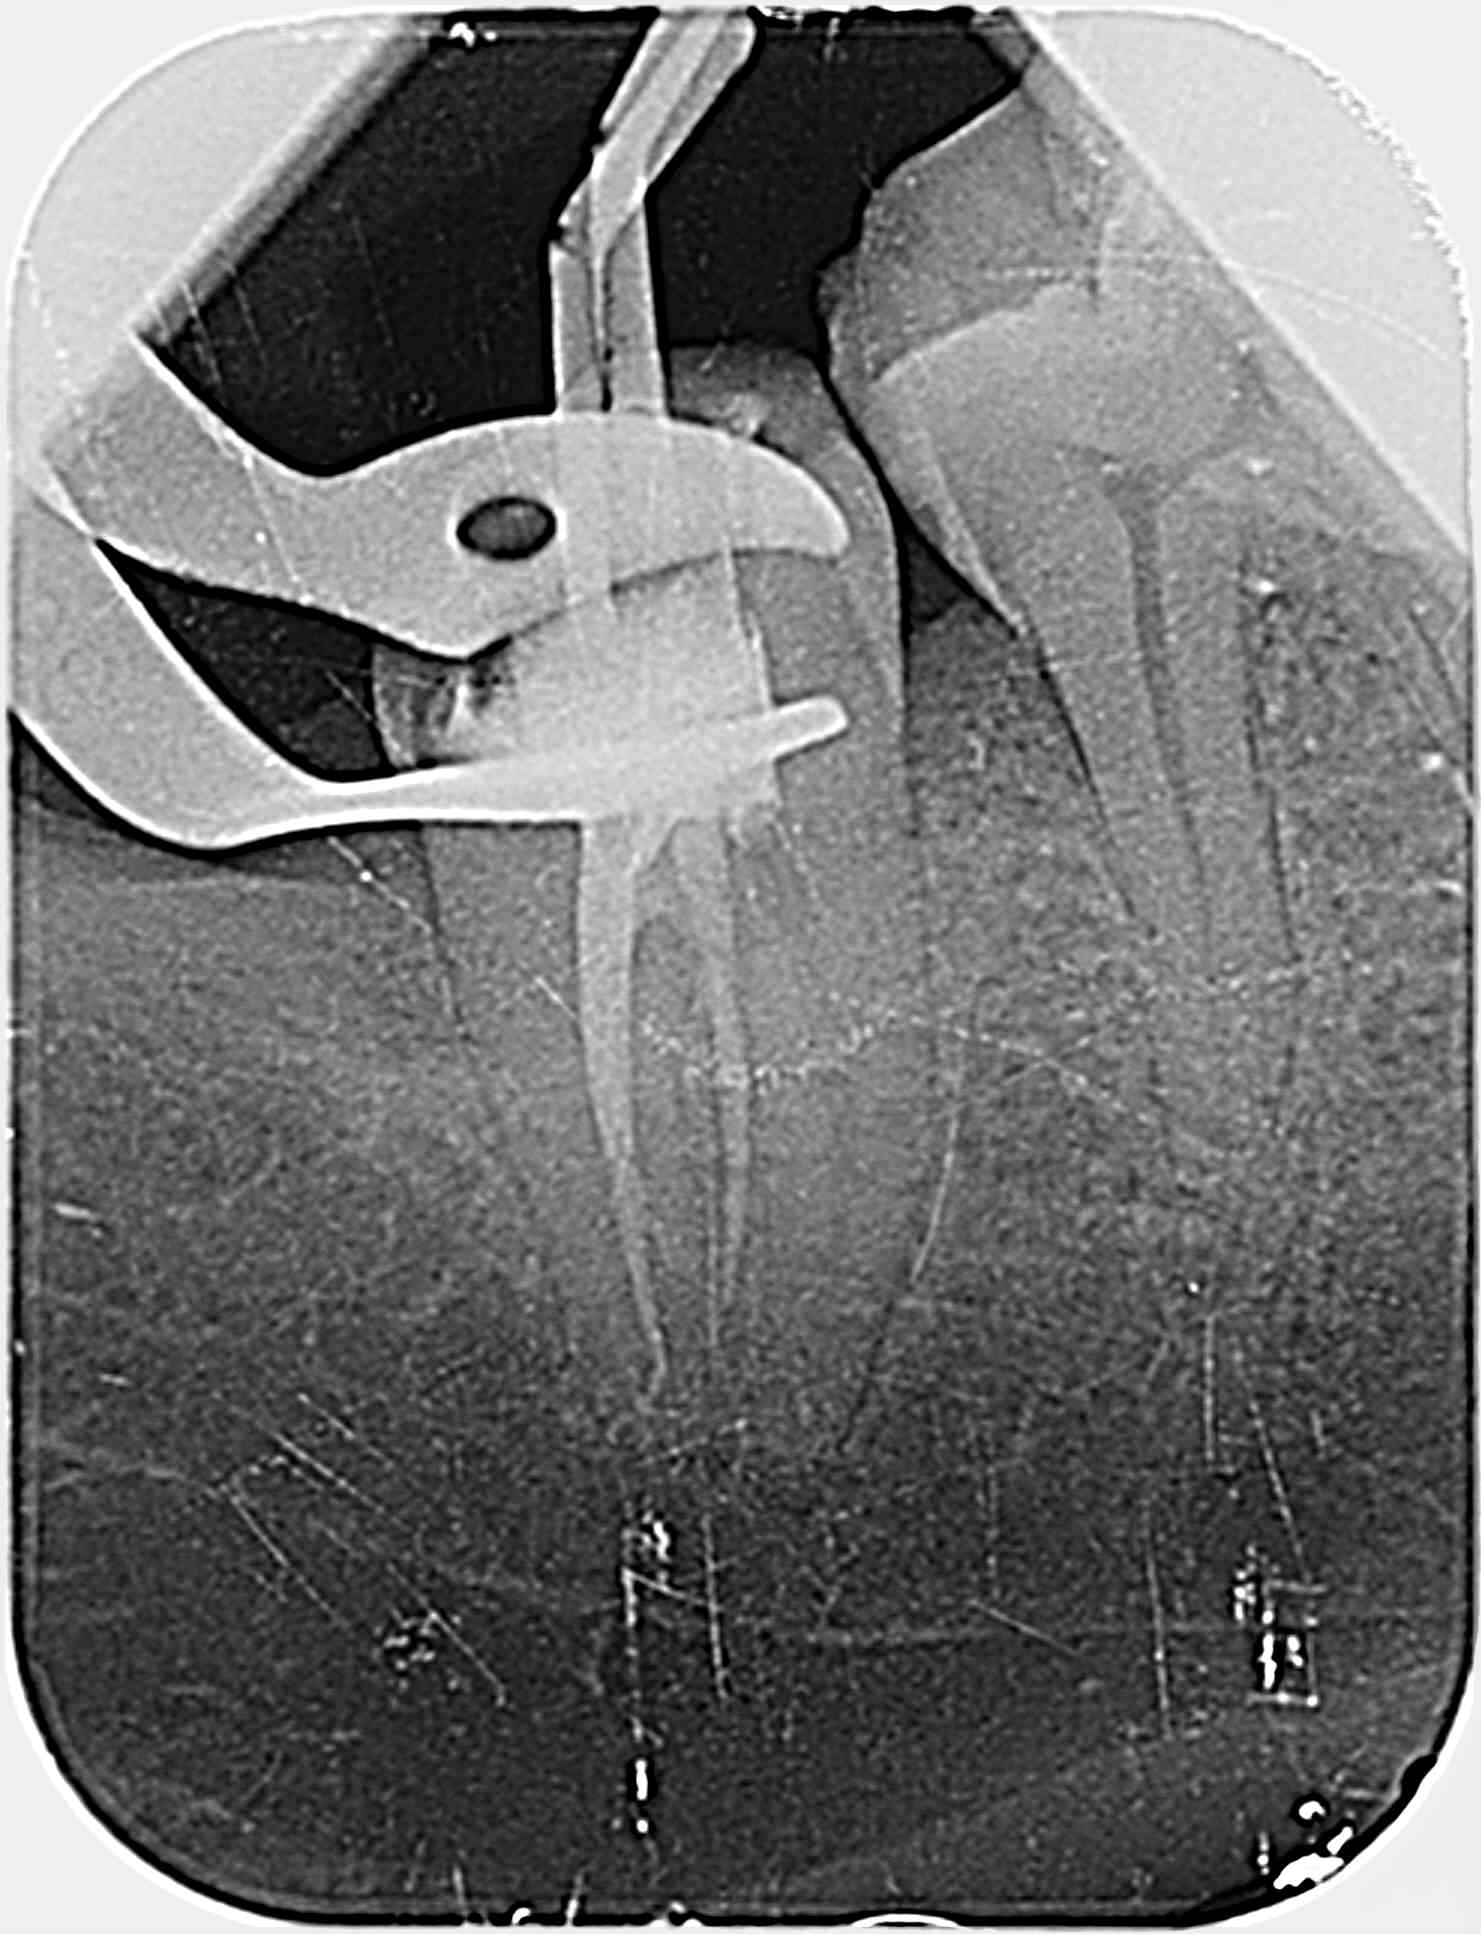

Je fais une radio per-op avec deux cônes de gutta fins de diamètre 20 4% dans les deux canaux mésiaux et … surprise…

Qu'en pensez-vous ?

1/Mon ML correspond a un canal secondaire qui va du plancher pulpaire vers l'espace interdentaire ? Ou bien ML dans racine que je ne vois pas (je ferai des radios excentré prochaine fois)?

2/Comment obturer si petit canal secondaire vers espace interradiculaire ? gutta? MTA ?

merci pour vos réponses, Pour la perf, je ne pense pas… D'ailleurs sur la pré-op on semble voir quelque chose à l'endroit de ma future pseudo perf..?

@bagheerra : J'ai édité mon message puisque je me suis trompé dans ma question 1/, je parlais du ML et non du DV. Les deux cônes sont dans les mesiaux comme indiqué.